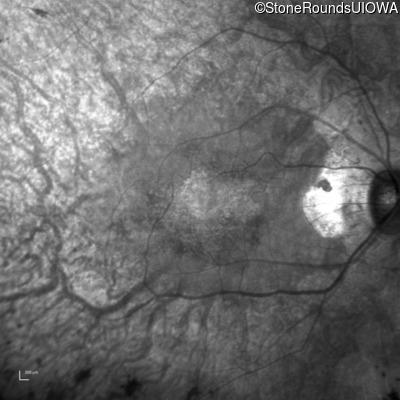

The clinical features supporting the diagnosis of MAK-associated autosomal recessive retinitis pigmentosa in this patient include: night blindness and constricted visual fields (with temporal predilection) as his earliest symptoms; bone-spicule-like pigmentation (with nasal predilection) and narrowed arterioles on fundus examination; loss of outer retinal structures on OCT; a similarly affected sibling; Jewish ethnicity; and, normally sighted parents.

Age at visit: 55 years